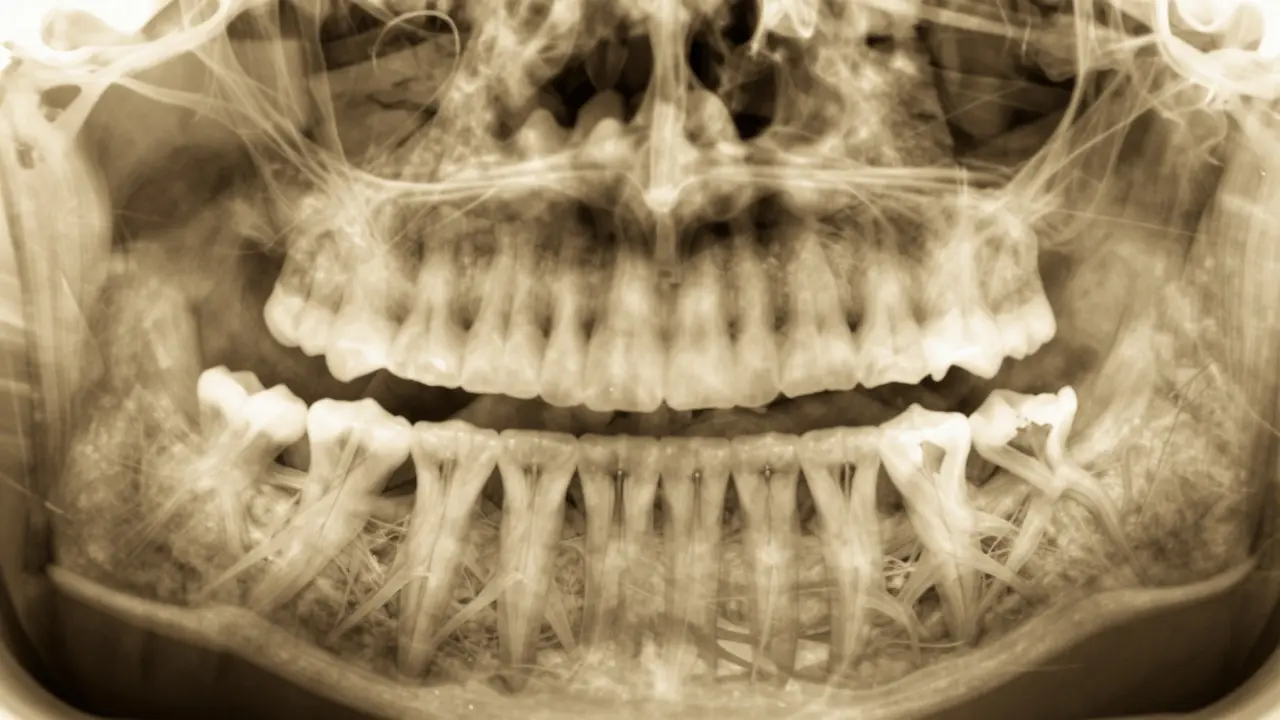

Rentgen zubního snímku s impaktovanými moudrými zuby v čelisti.

Zubní lékař provede prohlídku a pravděpodobně požádá o zubní rentgen. Rentgen zobrazí polohu moudrých zubů a zda jsou impaktované. Podle výsledků rozhodne, zda je třeba zub vyjmout. Většinou se extrakce provádí v ambulantním prostředí a trvá zhruba 30 minut. Po operaci vám lékař doporučí odpočinek a specifickou péči o ústa.

Proč je potřeba zubní rentgen pro kontrolu moudrých zubů?

Zubní rentgen je nezbytný, protože umožňuje lékaři vidět polohu moudrých zubů pod dásními a v čelisti. Bez rentgenu nelze určit, zda jsou zuby impaktované nebo zda hrozí poškození sousedních zubů. Moderní digitální rentgeny používají minimální dávku záření a jsou bezpečné pro pacienty.